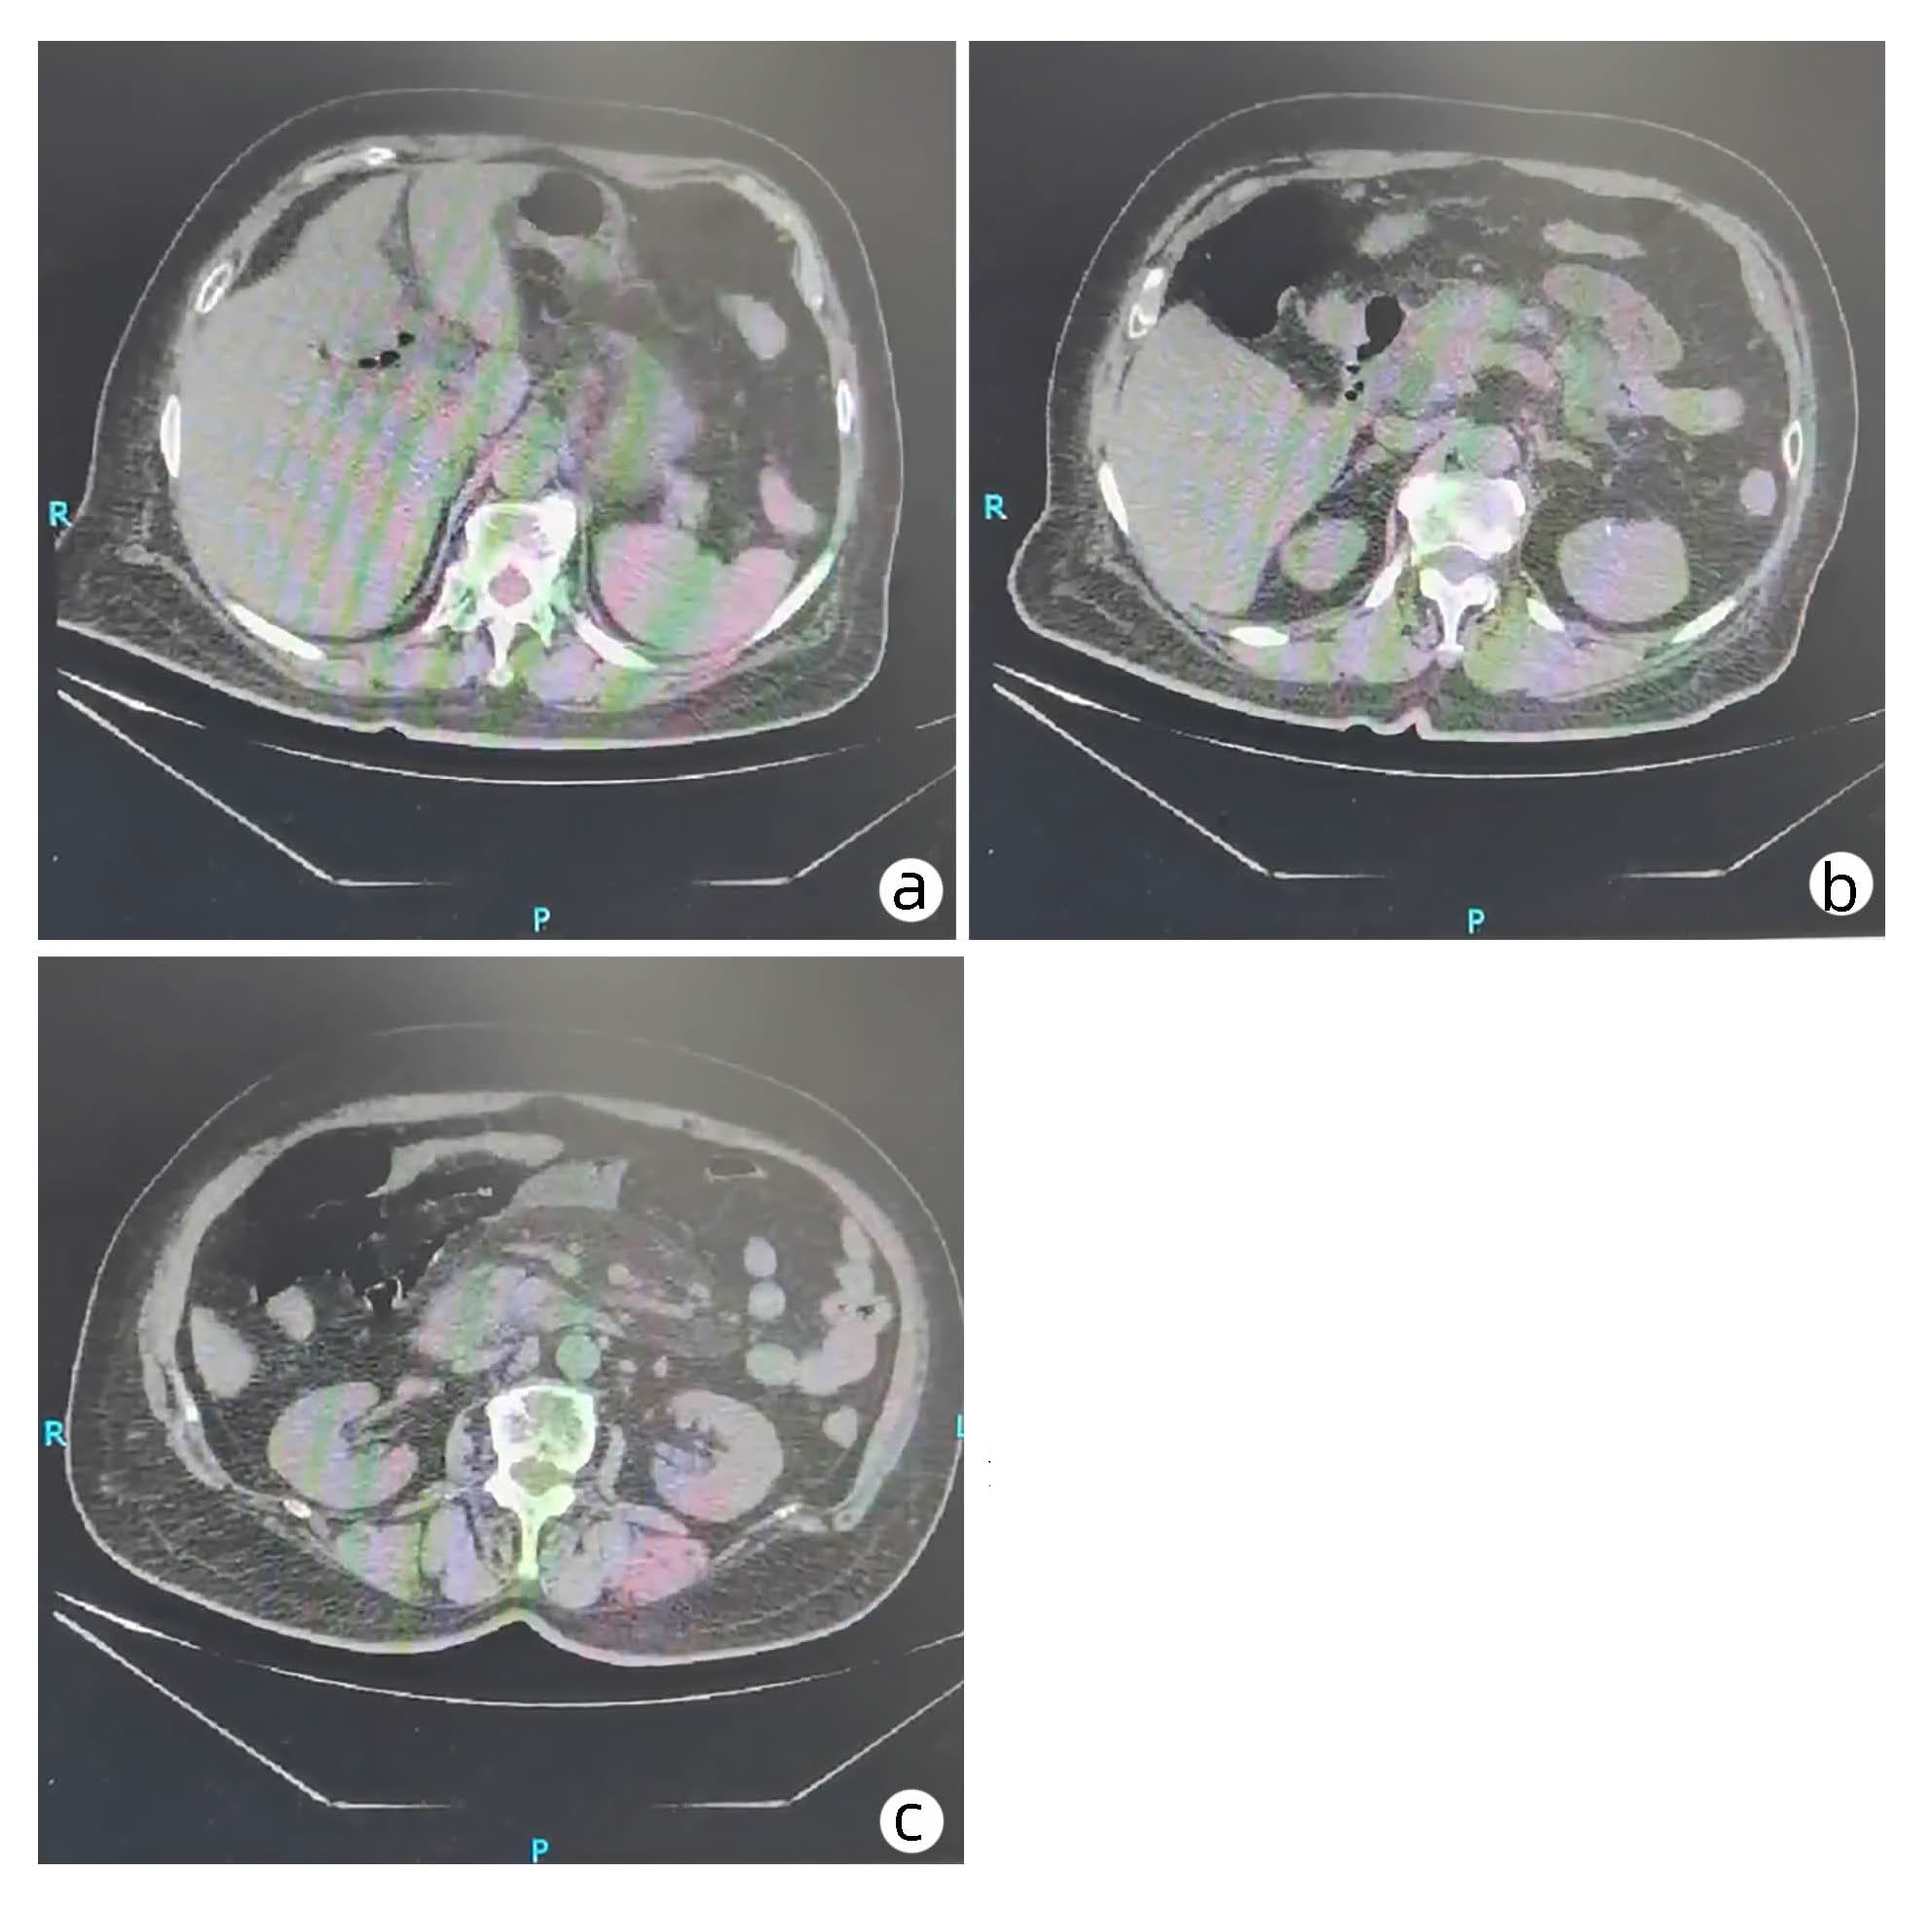

A case of atypical hepatic hemangioma misdiagnosed as hepatic cystadenoma

Sha WANG, Yanli ZHANG, Yuanyuan CHEN, Qinqin MA, Junqiang LEI

2023, 39(5): 1154-1156. DOI: 10.3969/j.issn.1001-5256.2023.05.023

Abstract(975) HTML (232) PDF (2557KB)(82)

Abstract: